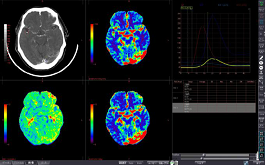

MR BRAIN PERFUSION

Analyzes blood flow using contrasted MR images scanned at the same cross-section, showing changes over time.

COMPUTED DWI

Creating specific b-value images and using the calculated ADC map enables comprehensive analysis of lesion and diffusion characteristics.